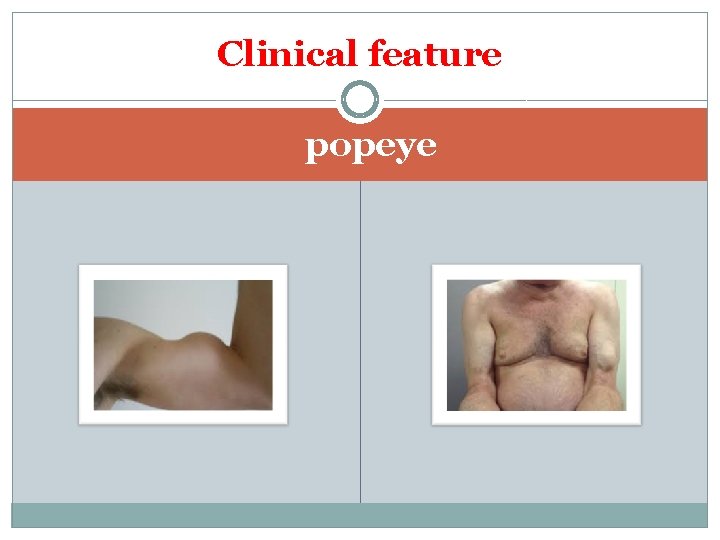

Clinical feature popeye